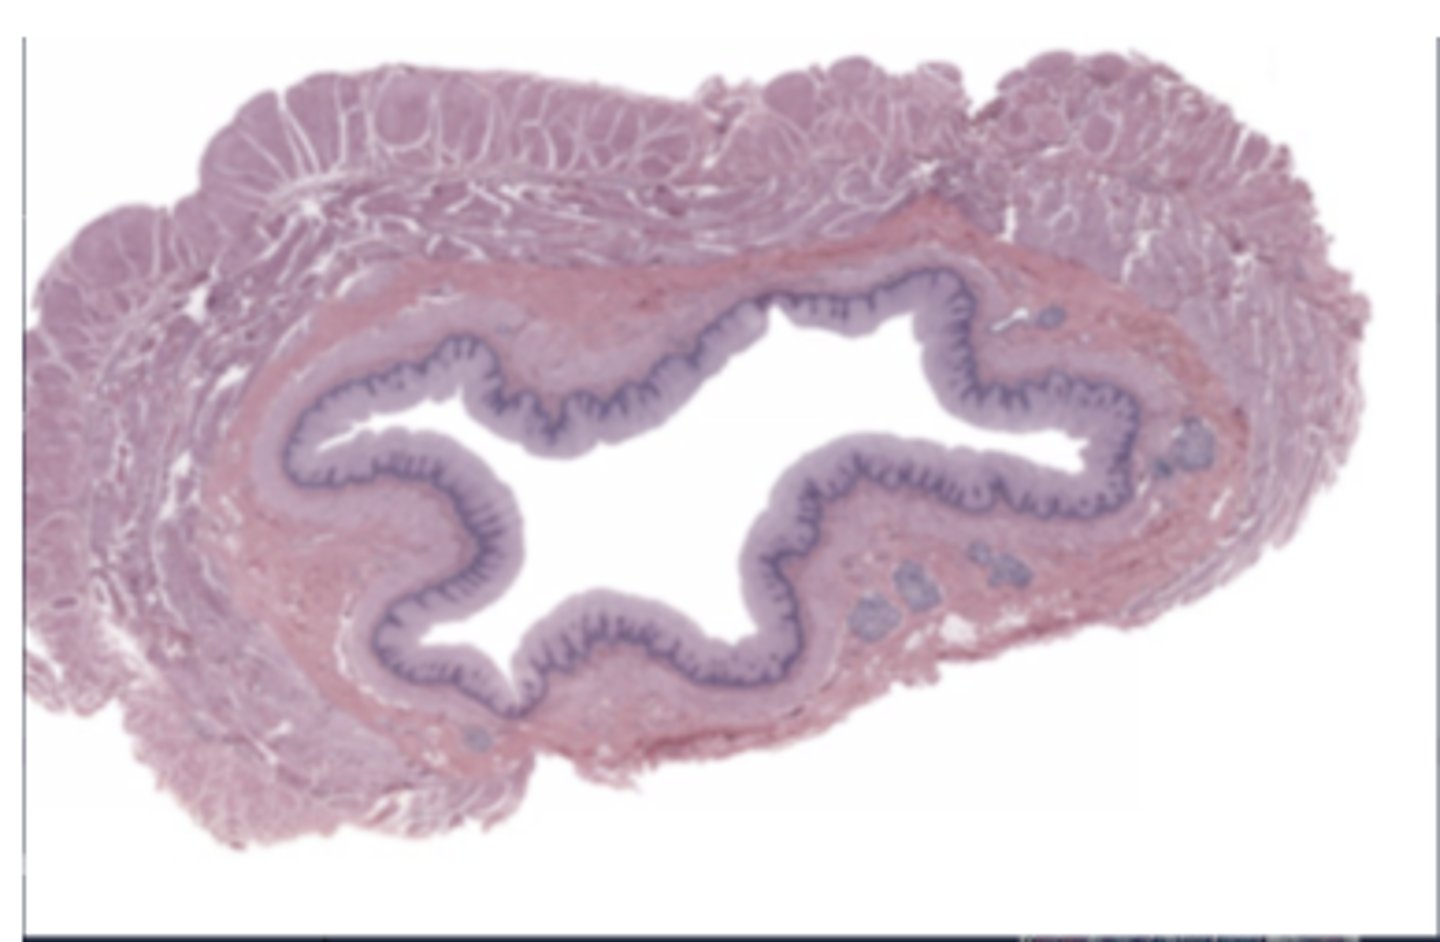

seminal vesicle

Brunner's gland